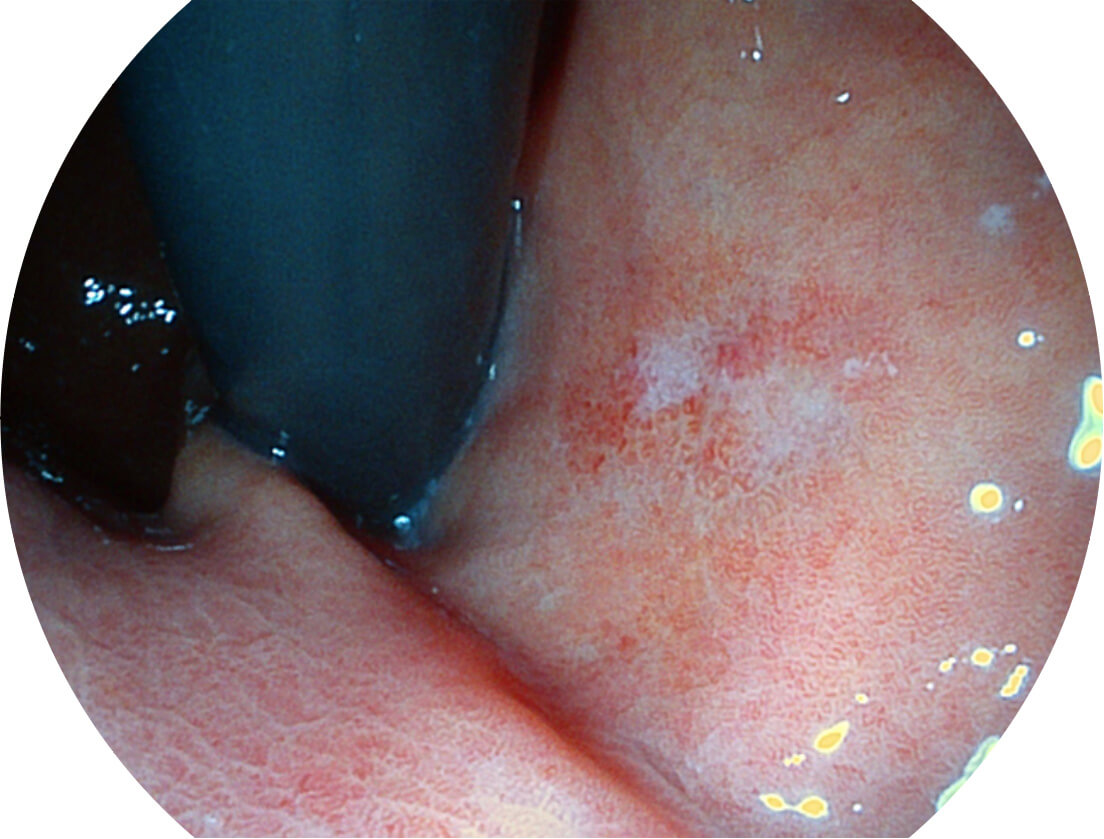

圖像具有高亮度、高黏膜血管顏色對比度的特點(diǎn),且不改變粘液、食物殘?jiān)?、糞便的基本顏色,可在中遠(yuǎn)景下進(jìn)行觀察,助力消化道早期疾病的診斷。

• 白光圖像 SFI圖像